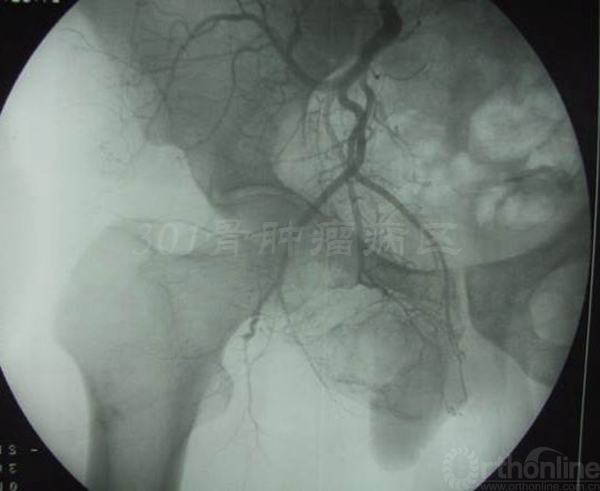

患者女性,术前X片提示:左侧骨盆Ⅱ+Ⅲ区溶骨性改变,诊断考虑骨巨细胞瘤合并动脉瘤样骨囊肿。血管栓塞后行骨盆Ⅱ+Ⅲ区切除,股骨头旷置术。术后病理报告是骨巨细胞瘤恶变,故行化疗6个月。术后13年随访,患者有跛行,但行走自如。

血管栓塞